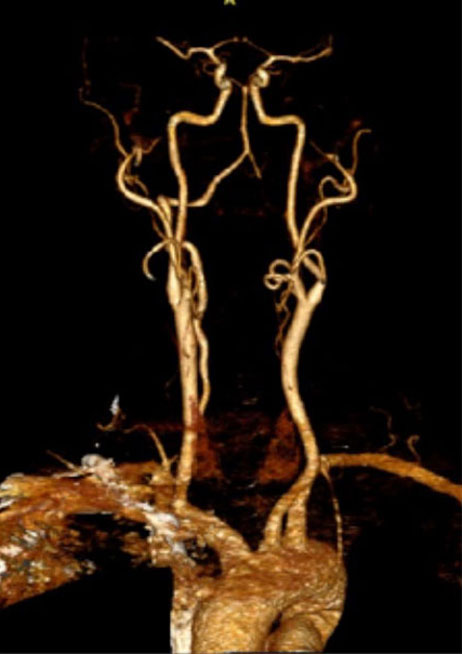

CTA of the neck and brain reveal that the left Vertebral Artery is completely occluded at approximately the C1-C2 level with extensive hypertrophic degenerative osseous changes from C1-C3. Retrograde flow into the post PICA left Vertebral Artery is observed from the co-dominant right Vertebral Artery which appears to be the primary supply into the basilar circulation. No significant Posterior Communicating arteries are observed on either the right or left Carotid Artery on the CTA imaging (Figure 1).